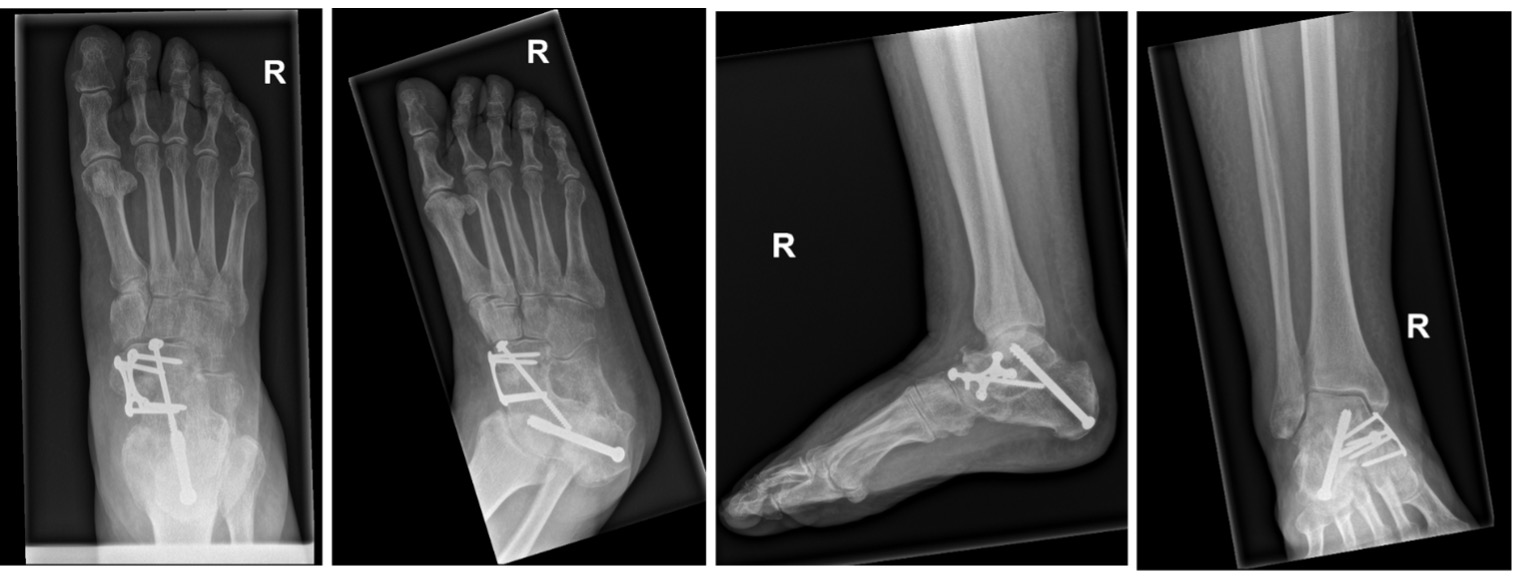

Stage IIA: Medialising calcaneal osteotomy + FDL transfer (Fig 9,10)

Figure 10a: Intra-op images (of Figure 7) showing calcaneal shift and correction of alignment

Figure 10b: Post-op standing radiographs (of Figure 7) showing restored talar head coverage and Meary’s angle